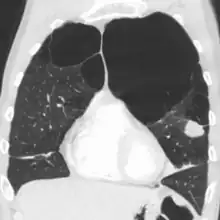

A chest X-ray and complete blood count may be useful to exclude other conditions at the time of diagnosis.[82] Characteristic signs on X-ray are hyperinflated lungs, a flattened diaphragm, increased retrosternal airspace, and bullae, while it can help exclude other lung diseases, such as pneumonia, pulmonary edema, or a pneumothorax.[83] A high-resolution CT scan of the chest may show the distribution of emphysema throughout the lungs and can also be useful to exclude other lung diseases.[25] Unless surgery is planned, however, this rarely affects management.[25] A saber-sheath trachea deformity may also be present.[84] An analysis of arterial blood is used to determine the need for oxygen; this is recommended in those with an FEV1 less than 35% predicted, those with a peripheral oxygen saturation less than 92%, and those with symptoms of congestive heart failure.[24] In areas of the world where alpha-1 antitrypsin deficiency is common, people with COPD (particularly those below the age of 45 and with emphysema affecting the lower parts of the lungs) should be considered for testing.[24]